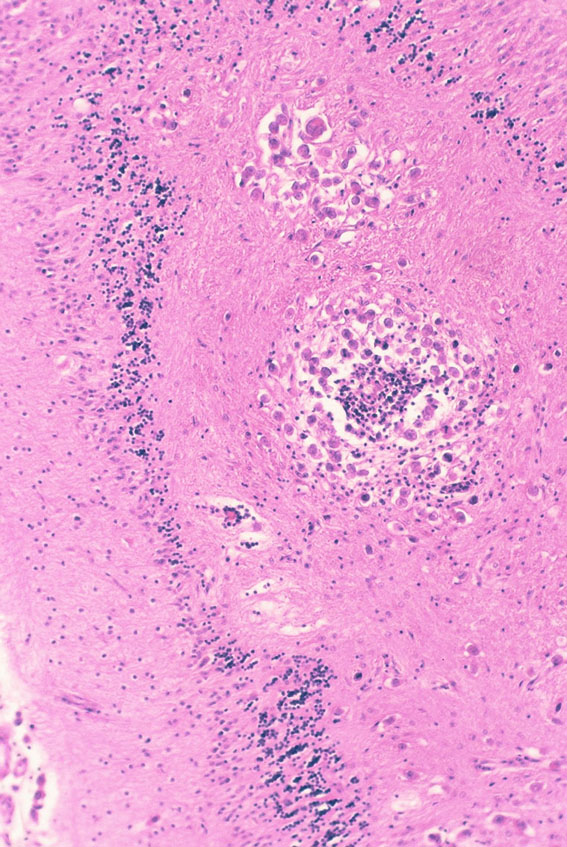

1992年の剖検所見

大脳表面,脳幹部,脊髄くも膜下腔には腫瘍が見当たりませんが,側脳室を充満するように腫瘍が増殖しています。

側脳室壁に結節状の腫瘍が無数に認められます。これは今日では,内視鏡による脳室内観察で見ることができるものです。

上方が側脳室側です。脳との境にある脳室上衣 ependyumの下に腫瘍細胞が這うように浸潤しています。そこから血管周囲 Virchow-Robin spaceを通って脳深部に浸潤しています。

大脳深部(左)と小脳深部(右)には髄質血管に沿って浸潤します。これは髄芽腫などと同様の脳浸潤所見です。